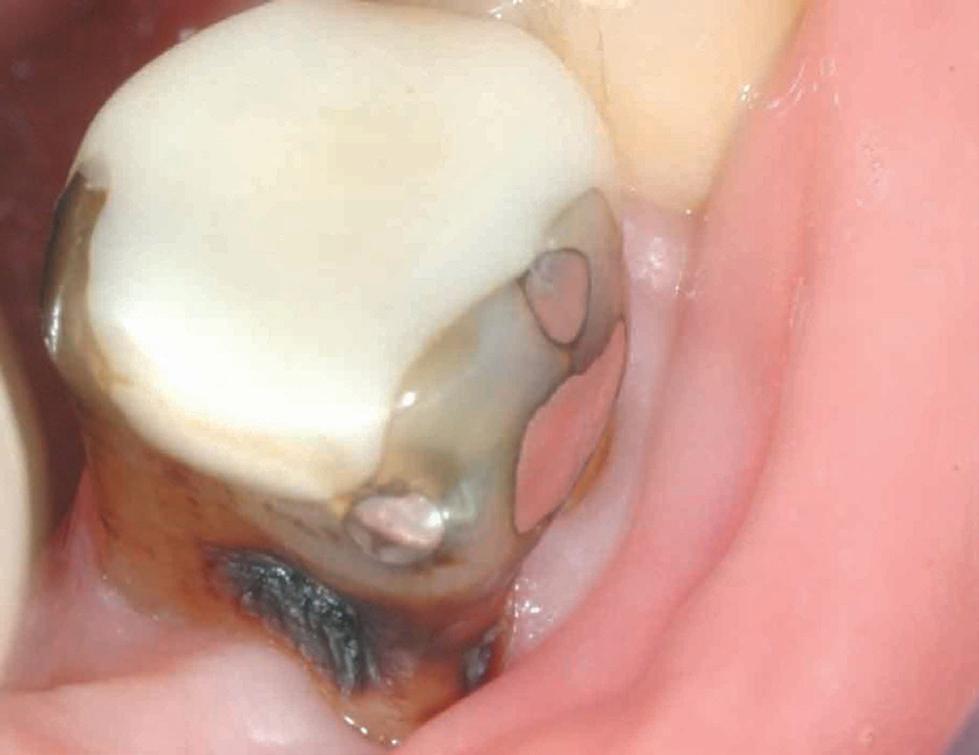

Estelite Asteria (Tokuyama)One of my favourite composite resin materials is Asteria which is a light-cured radiopaque composite for universal use. It considerably simplifies multilayer techniques yet delivers outstanding aesthetics with excellent polishability. Unlike mul tilayer techniques used with conventional composites, Asteria uses only 2 layers for optimal results without compromising aesthetics. The microstructure of the material produces a light diffusion that helps blend in with the natural tooth structure. The chameleon like nature of the material allows a blending of the materials to natural tooth structure and it allows excellent polishability which retains its lustre over time.